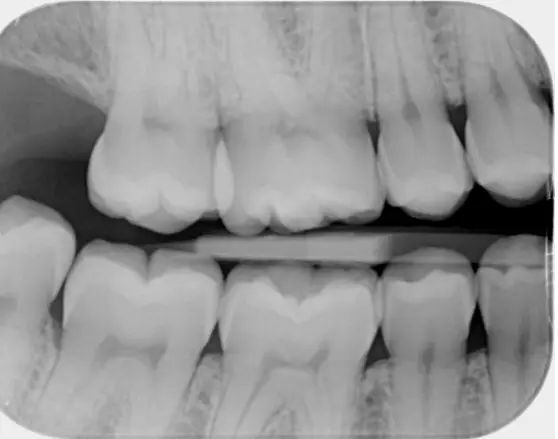

1. Bitewing røntgen (BW)

• Formål

Bitewing-røntgen bruges bl.a. til at kontrollere om der skulle være aktive huller mellem tænderne, til at kontrollere højde og hældning af knoglevævet samt kontrollere under kroner og fyldninger.

• Hvordan det tages

Du bider på et lille filmkort på en holder, som placeres i munden. Ved at bide på holderen midt for filmkortet, fås et billede gående vinkelret på de bagerste tænder i munden i både over- og undermund.

• Hvornår det er indiceret

Bitewing røntgen bruges primært til at opdage huller, vurdering af tandkødssundhed ud fra knogleniveauet, kontrol af generel tandstatus samt til at følge op på tidligere tandbehandlinger.

Bitewing-røntgenbillede optaget hos tandlægerne Ølandshus på Amager.